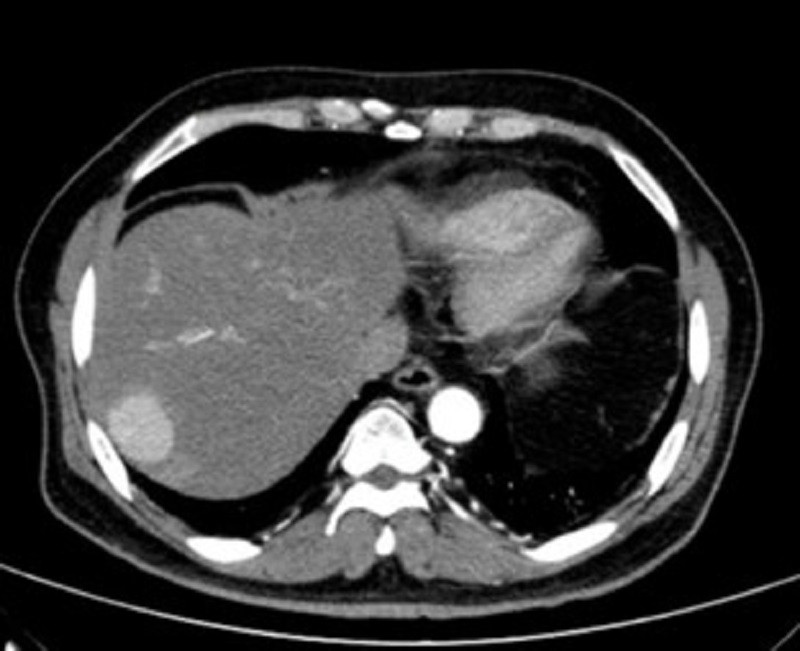

| Hình ảnh kiểm tra phát hiện khối ung thư nằm vị trí sát rìa gan của người bệnh |

Bác sĩ Hàng Thế Cơ, Khoa Ngoại Tổng Quát bệnh viện này cho biết, khối u gan nằm ở vị trí hạ phân thùy VII của bệnh nhân có kích thước 33x35 mm. Bệnh nhân được sinh thiết khối u dưới hướng dẫn siêu âm và chẩn đoán xác định là ung thư gan nguyên phát. Sau chẩn đoán, bệnh nhân đã được chỉ định cắt phần gan có khối ung thư. Cuộc mổ diễn ra thuận lợi, sau phẫu thuật sức khỏe người bệnh đã bình phục tốt. Nhờ phát hiện sớm nên khối chưa gây ảnh hưởng đến sức khỏe của người bệnh.